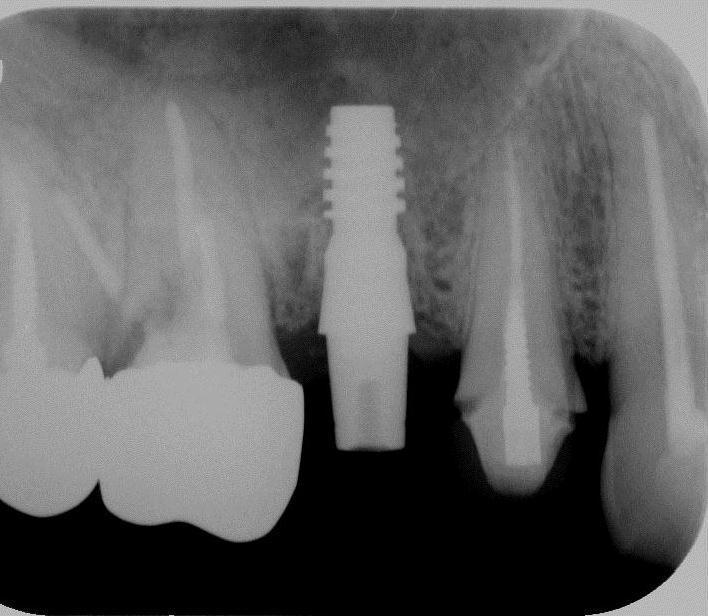

【審美歯科 前歯セラミック症例紹介②】

●治療箇所

左右2番目のは変色あり(歯の神経が死んだ状態)

●費用

セラミッククラウン

【オールセラミックe-max】

上記治療費用目安

初診検査 3500

グラスファイバーコア 10000×2本

仮歯 2本 2000×2本

歯型 5500

セラミッククラウン 69800×2本

調整装着費用 5500

治療回数目安 3回~6回

■ポイント■

前歯はオールセラミック(e-max,ジルコニアボンドセラミック)

が機能性・耐久性・審美性の面でゴールドスタンダード